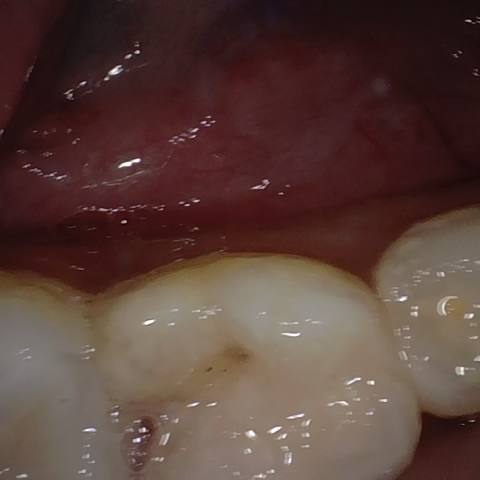

Annotated as "Good"